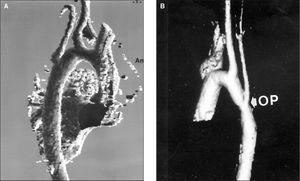

Figura 4. Angiorresonancia tridimensional. Proyección sagital oblicua. Grupo A. Paciente de 15 años. Plastia de subclavia. Ligero aneurisma de la zona plastiada. Ausencia de la zona proximal de la subclavia.

Grupo B (tabla 3): Lo constituyen 33 pacientes. De ellos, 21 varones (63,6 %) y 12 mujeres (36,4 %); 21 (65,6 %) fueron corregidos antes del primer mes de vida. Todos presentaron recoartación precoz (fig. 5): una valoración con resonancia se realizó a los 11,4 ± 4,3 años (rango 2-23) y se obtuvieron índices diámetro istmo/diámetro aorta descendente a nivel del diafragma de 0,84 ± 0,1, diámetro zona intervenida/diámetro aorta descendente a nivel del diafragma 0,82 ± 0,11 (rango 0,53-1) inferiores al grupo A. En un total de 11 pacientes se confirmó el diagnóstico con angiorresonancia tridimensional con gadolinio. En la valoración final se pudo observar una reestenosis en cinco pacientes, tres corregidas antes de los dos meses (índices 0,55, 0,53 y 0,73) con técnica término-terminal con angioplastias y stents en dos a los 16 años. Otros dos pacientes fueron intervenidos inicialmente en el primer mes, uno con 19 años operado con técnica término-terminal más dos plastias y stent con índice de 0,54 y otro con parche más plastia y prótesis con obstrucción grave pendiente de actuación. Tras 43 reintervenciones, en 5 del grupo B (15,1 %) persiste la obstrucción, mientras que existe en sólo dos del grupo A a largo plazo.

Figura 5. Angiorresonancia tridimensional. Reconstrucción. Grupo B. Proyección sagital oblicua. Paciente de 18 años. Técnica término-terminal en el primer mes de vida más dos angioplastias y dos stents. Hipoplasia grave del arco en zonas proximal y distal, y del istmo. Ausencia del nacimiento de carótida y subclavia izquierdas producida por el stent.